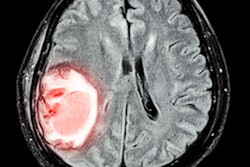

The notion that stroke care could one day take to the skies seems more likely now than ever. Researchers from Australia have launched a new research program tasked with developing portable brain CT scanners that can be installed onboard aircraft to give rural areas access to faster stroke intervention.

One of the main challenges facing the realization of this proposition has been reducing the weight of a standard CT scanner, which weighs approximately 1 ton. Donnan, Davis, and colleagues have been looking at the latest innovations in CT technology and other potential imaging options involving electromagnetic waves to determine the best way to develop more lightweight scanners that could be taken airborne.